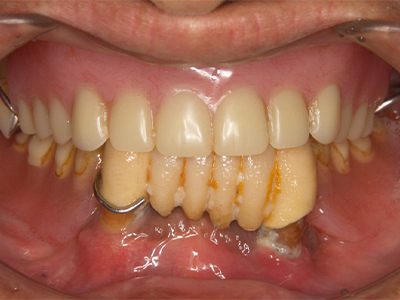

治療前後写真

治療前

治療後

年齢・性別

43歳・女性

来院理由

銀歯を白い歯に治したい

治療内容

マイクロスコープ下でカリエス除去後、セラミック(インレー・クラウン・ラミネートべニア)で全顎的に修復しメンテ移行

治療期間

約2ヶ月

費用

- ラミネートべニア(2本)297,000円

- セラミックインレー(2歯)143,000円

- セラミッククラウン(6歯)1,023,000円

リスク・副作用

再補綴時の歯髄損傷リスク

残存歯質が少ない場合の破折リスク

医院コメント

色・形態・咬合を総合的に整え、審美性と機能性のバランスを長期目線で最適化。